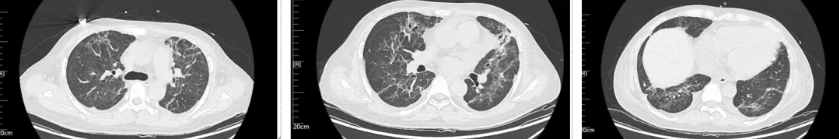

经过治疗后患者病情逐渐好转,呼吸机需氧浓度及PEEP逐渐下调,复查血气氧和指数逐渐好转,9月17日复查胸部CT(见图4),氧合指数165,予拔除气管插管,改日间高流量(流速 40L/min,氧浓度60%)与夜间无创呼吸机辅助通气(IPAP12cmH2O EPAP 5cmH2O FiO2 45%)交替,复查血气氧和指数P/F 182。予逐渐下调氧浓度复查氧和指数进一步升高(见图5),监测患者外周血感染指标超敏C反应蛋白降至基本正常(见图6)。调整鼻导管吸氧,10月7日复查胸部CT双肺慢性及间质改变较前明显吸收(见图7)。监测患者外周血KL-6水平较前明显下降(见图8)。

图4 患者2025年9月17日复查胸部CT